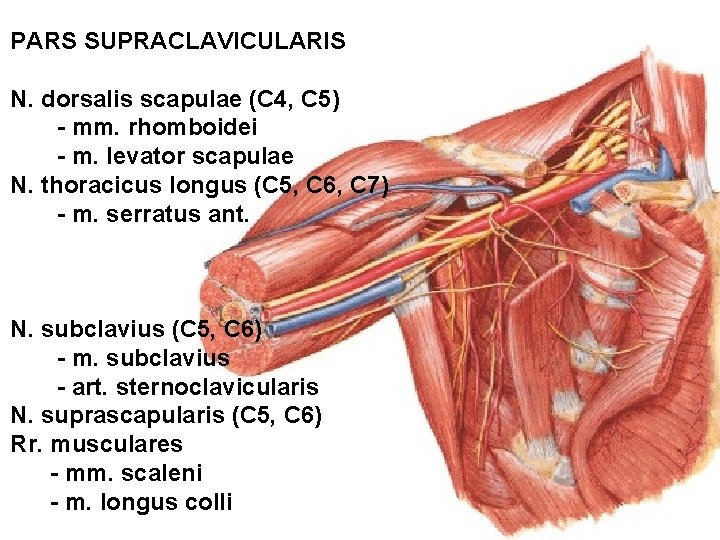

PARS SUPRACLAVICULARIS N. dorsalis scapulae (C 4, C 5) - mm. rhomboidei - m. levator scapulae N. thoracicus longus (C 5, C 6, C 7) - m. serratus ant. N. subclavius (C 5, C 6) - m. subclavius - art. sternoclavicularis N. suprascapularis (C 5, C 6) Rr. musculares - mm. scaleni - m. longus colli